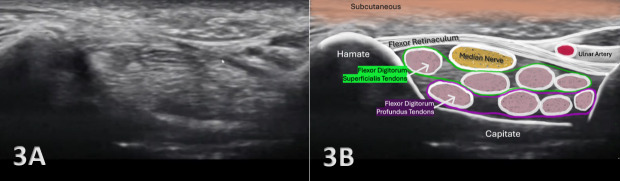

正中神经是前臂和手腕的重要结构,负责运动和感觉功能。神经损伤的准确诊断对于制定适当的治疗计划和优化患者预后至关重要。虽然磁共振成像(MRI)和神经传导研究(NCS)是神经评估的金标准,但诊断肌肉骨骼(MSK)超声提供了一种便携式、实时、经济高效的替代方法,在康复和运动医学领域越来越受欢迎。MSK超声已经成为评估正中神经病理的一种有价值的、非侵入性的成像方式,包括腕管综合征(CTS)、神经卡压和创伤性神经损伤。本文综述了MSK超声在评估正中神经损伤中的应用,包括其解剖、常见损伤模式、超声技术以及专业康复的临床意义。通过将MSK超声整合到临床实践中,提供者可以提高诊断的准确性,监测愈合进展,并指导康复策略以获得最佳患者结果。

The median nerve is a crucial structure in the forearm and wrist, responsible for motor and sensory functions. Accurate diagnosis of nerve injury is essential for appropriate treatment planning and optimizing patient outcomes. Although magnetic resonance imaging (MRI) and nerve conduction studies (NCS) are the gold standard for nerve assessment, diagnostic musculoskeletal (MSK) ultrasound offers a portable, real-time, and cost-effective alternative that is gaining traction in rehabilitation and sports medicine settings. MSK ultrasound has emerged as a valuable, non-invasive imaging modality for evaluating median nerve pathology, including carpal tunnel syndrome (CTS), nerve entrapment, and traumatic nerve injuries. This article reviews the utility of MSK ultrasound in evaluating the median nerve injury, including its anatomy, common injury patterns, sonographic techniques, and clinical implications for professional rehabilitation. By integrating MSK ultrasound into clinical practice, providers can improve the accuracy of diagnosis, monitor healing progression, and guide rehabilitation strategies for optimal patient outcomes.